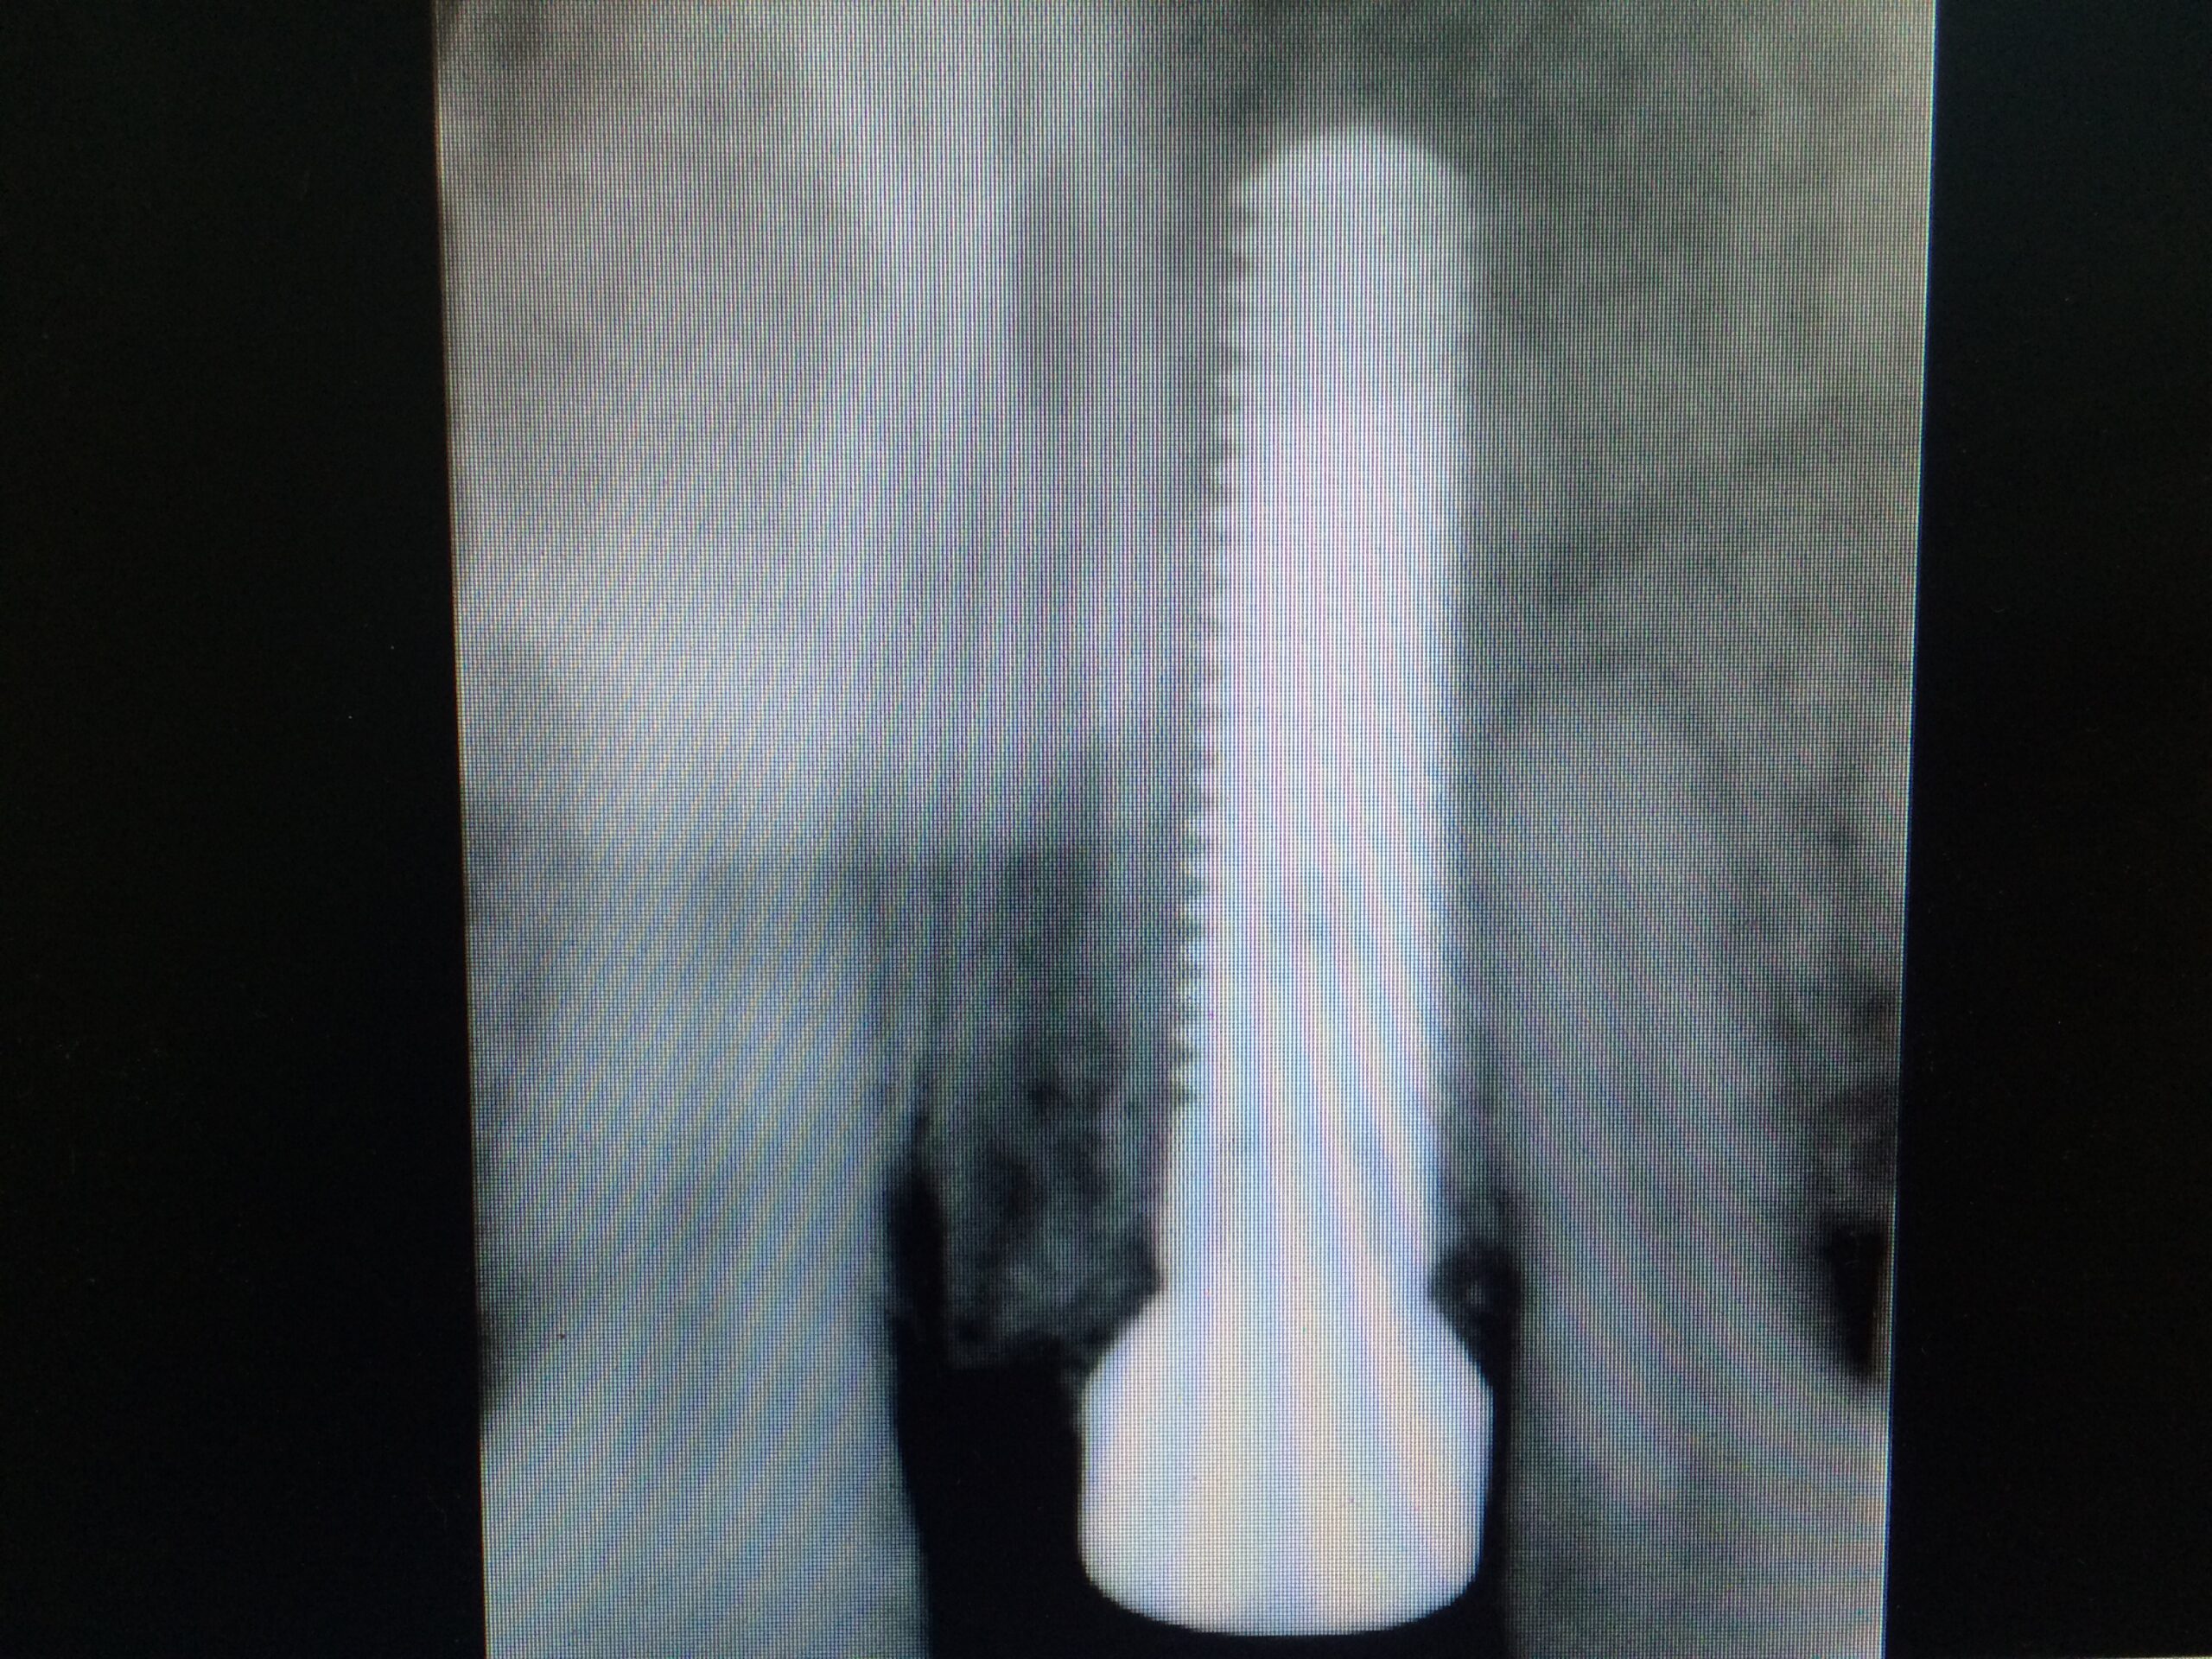

Un implant dentaire est une racine artificielle en titane qui remplace la racine manquante d’une dent naturelle. Il est placé dans la mâchoire inférieure ou supérieure pour remplacer une ou plusieurs dents. Après la période de cicatrisation osseuse, la couronne est fixée au-dessus de l’implant.

→ Pose du ou des implants

Durant cette étape, le praticien pose les implants dentaires pour remplacer les racines manquantes. À l’issue de cette intervention, vous sentirez des implants couverts par la gencive, et qu’ils sont mis en “nourrice” : cela permet à l’os de cicatriser autour des implants.

→ Pose de la prothèse définitive

Après la cicatrisation de l’os et de la gencive, une simple prise d’empreinte comme sur une dent naturelle permettra la réalisation d’une prothèse naturelle et fonctionnelle.